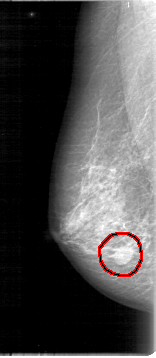

D_4012_1.RIGHT_CC

RIGHT_CC LINES 5281 PIXELS_PER_LINE 2086 BITS_PER_PIXEL 12 RESOLUTION 43.5 OVERLAY

FILE: D_4012_1.RIGHT_CC.OVERLAY

TOTAL_ABNORMALITIES 1

ABNORMALITY 1

LESION_TYPE MASS SHAPE OVAL MARGINS OBSCURED

ASSESSMENT 0

SUBTLETY 5

PATHOLOGY BENIGN

TOTAL_OUTLINES 1

BOUNDARY